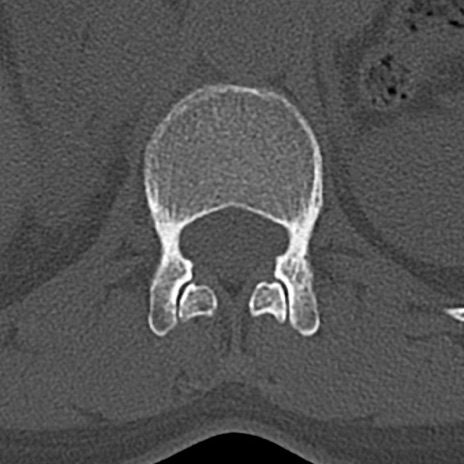

腰椎CT

横断像と矢状断像